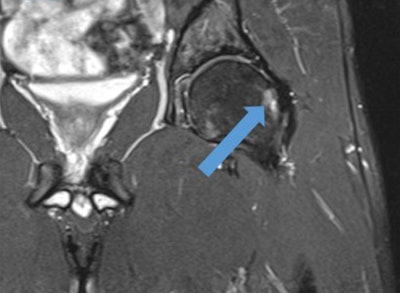

Coronal T2-weighted fat-suppressed MR image of the hip shows cam-type femoroacetabular impingement in a player. Note the increased signal intensity of subchondral femur head due to edema and cystic changes (blue arrow).

Coronal T2-weighted fat-suppressed MR image of the hip shows cam-type femoroacetabular impingement in a player. Note the increased signal intensity of subchondral femur head due to edema and cystic changes (blue arrow)."MRI scans were reviewed for bone marrow edema in and around the pubic symphysis. Any abdominal wall, inguinal, femoral, or internal hernia was recorded," the authors wrote. "Tendinous injury involving the rectus abdominis and the adductor tendons (pectineus, adductor longus, adductor brevis, adductor gracilis, and adductor magnus) were reviewed. Tendon findings were classified as pathologic when there was a tendon enlargement, peritendinous fluid with or without intratendinous fluid signal intensity, partial tear, and complete disruption."